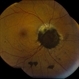

Choroidal Melanoma With Vitreous Seeding

Choroidal Melanoma

Underlying retinal choroidal melanoma with dense vitreous seeding of choroidal melanoma cells.